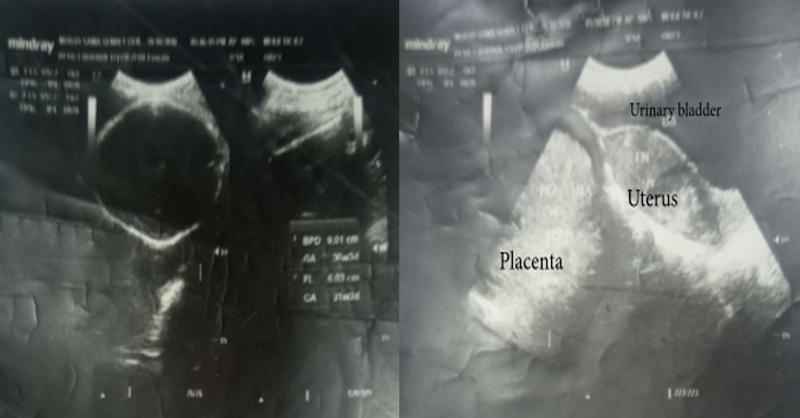

- Advanced Abdominal Ectopic Pregnancy in a 26 year old woman

Abdominal pregnancy is the rarest and extremely dangerous type of extrauterine pregnancy. (1) It has been estimated to account for nearly 1 to 1.4 percent of all ectopic pregnancies.(2) Early diagnosis of abdominal pregnancy is usually associated with a broad range of signs and symptoms.(3) The risk factors for abdominal pregnancy include; tubal da